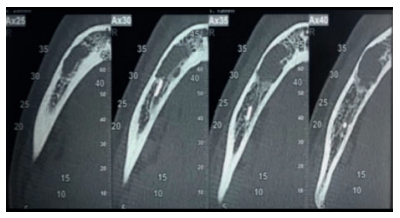

Análisis de los tejidos peri-implantarios en implantes anteriores: relación entre la presencia o ausencia de tabla ósea y el Pink Esthetic Score

Introducción: La dehiscencia es una pérdida de la cortical que deja expuesta parte de la raíz al medio oral. Se considera como un factor predisponente de las recesiones gingivales y, por tanto, de una alteración estética. El objetivo principal fue estudiar la relación entre la presencia o ausencia de la tabla ósea vestibular en implantes anteriores y el resultado estético valorado mediante el índice Pink Esthetic Score (PES). Los objetivos secundarios fueron analizar la opinión del paciente comparándolo además con lo valores de PES hallados por el evaluador principal.

Material y método: Se llevó a cabo un estudio analítico, longitudinal, retrospectivo, de cohortes en un grupo de 31 pacientes quienes llevaban implantes antero-superiores con un mínimo de 3 años de carga protésica. Se realizó un TAC para valorar la presencia/ausencia de tabla ósea junto con una exploración para evaluar el PES.

Resultados: El índice PES fue signifi cativamente más elevado (10,4 ± 2,3) en presencia de tabla ósea. La valoración del paciente tuvo una nota media global de 8,2 ± 1,6. No se halló correlación entre la opinión del paciente y la del evaluador.

Conclusiones: La ausencia de tabla ósea vestibular en implantes anteriores conlleva alteraciones estéticas de los tejidos peri-implantarios.